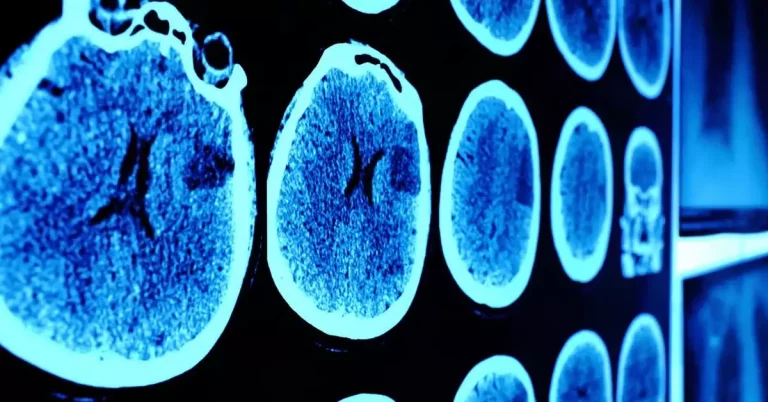

Spotlight On: Headache, MRI and Brain Imaging

When do you need brain imaging for your headache symptoms? Here are some key things you should know before talking to your doctor about